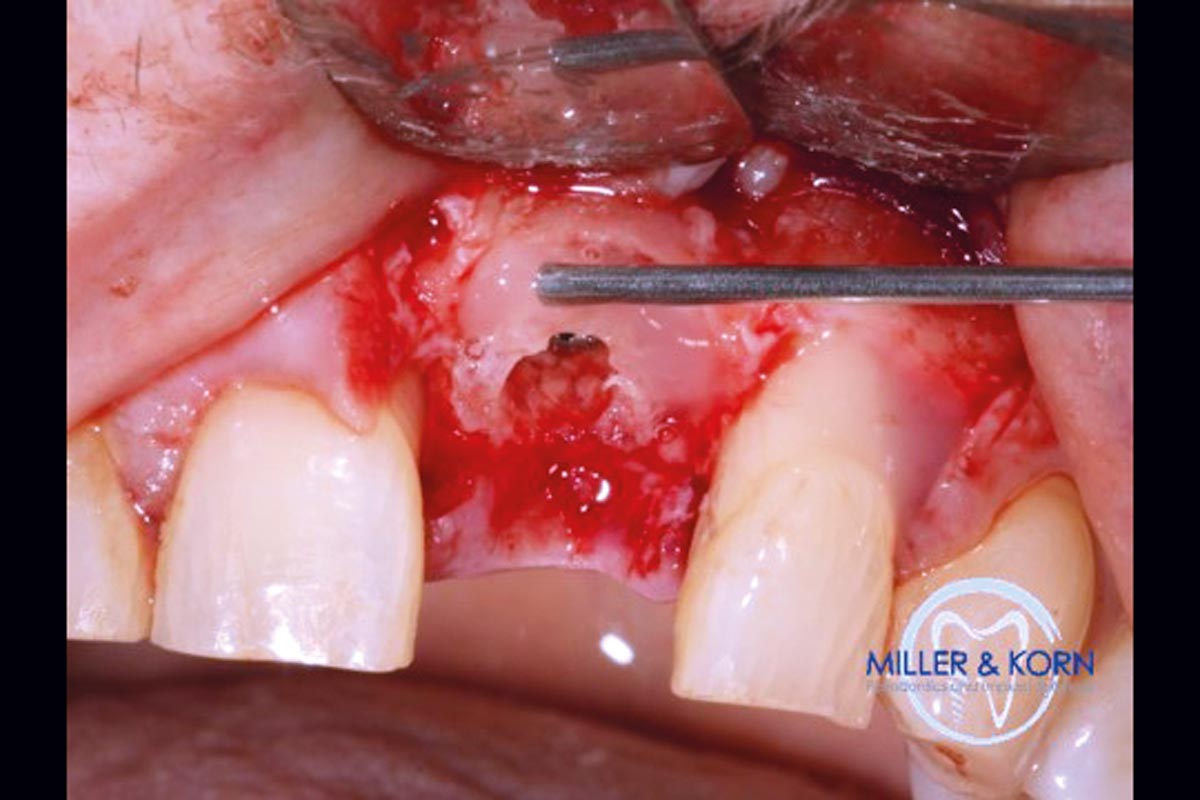

04/39 - Preparation of a full thickness flap and careful debridementImmediate implant placement and correction of horizontal and vertical bone loss using an allograft bone ring, cerabone® and Jason® membrane - Drs. Miller and Korn